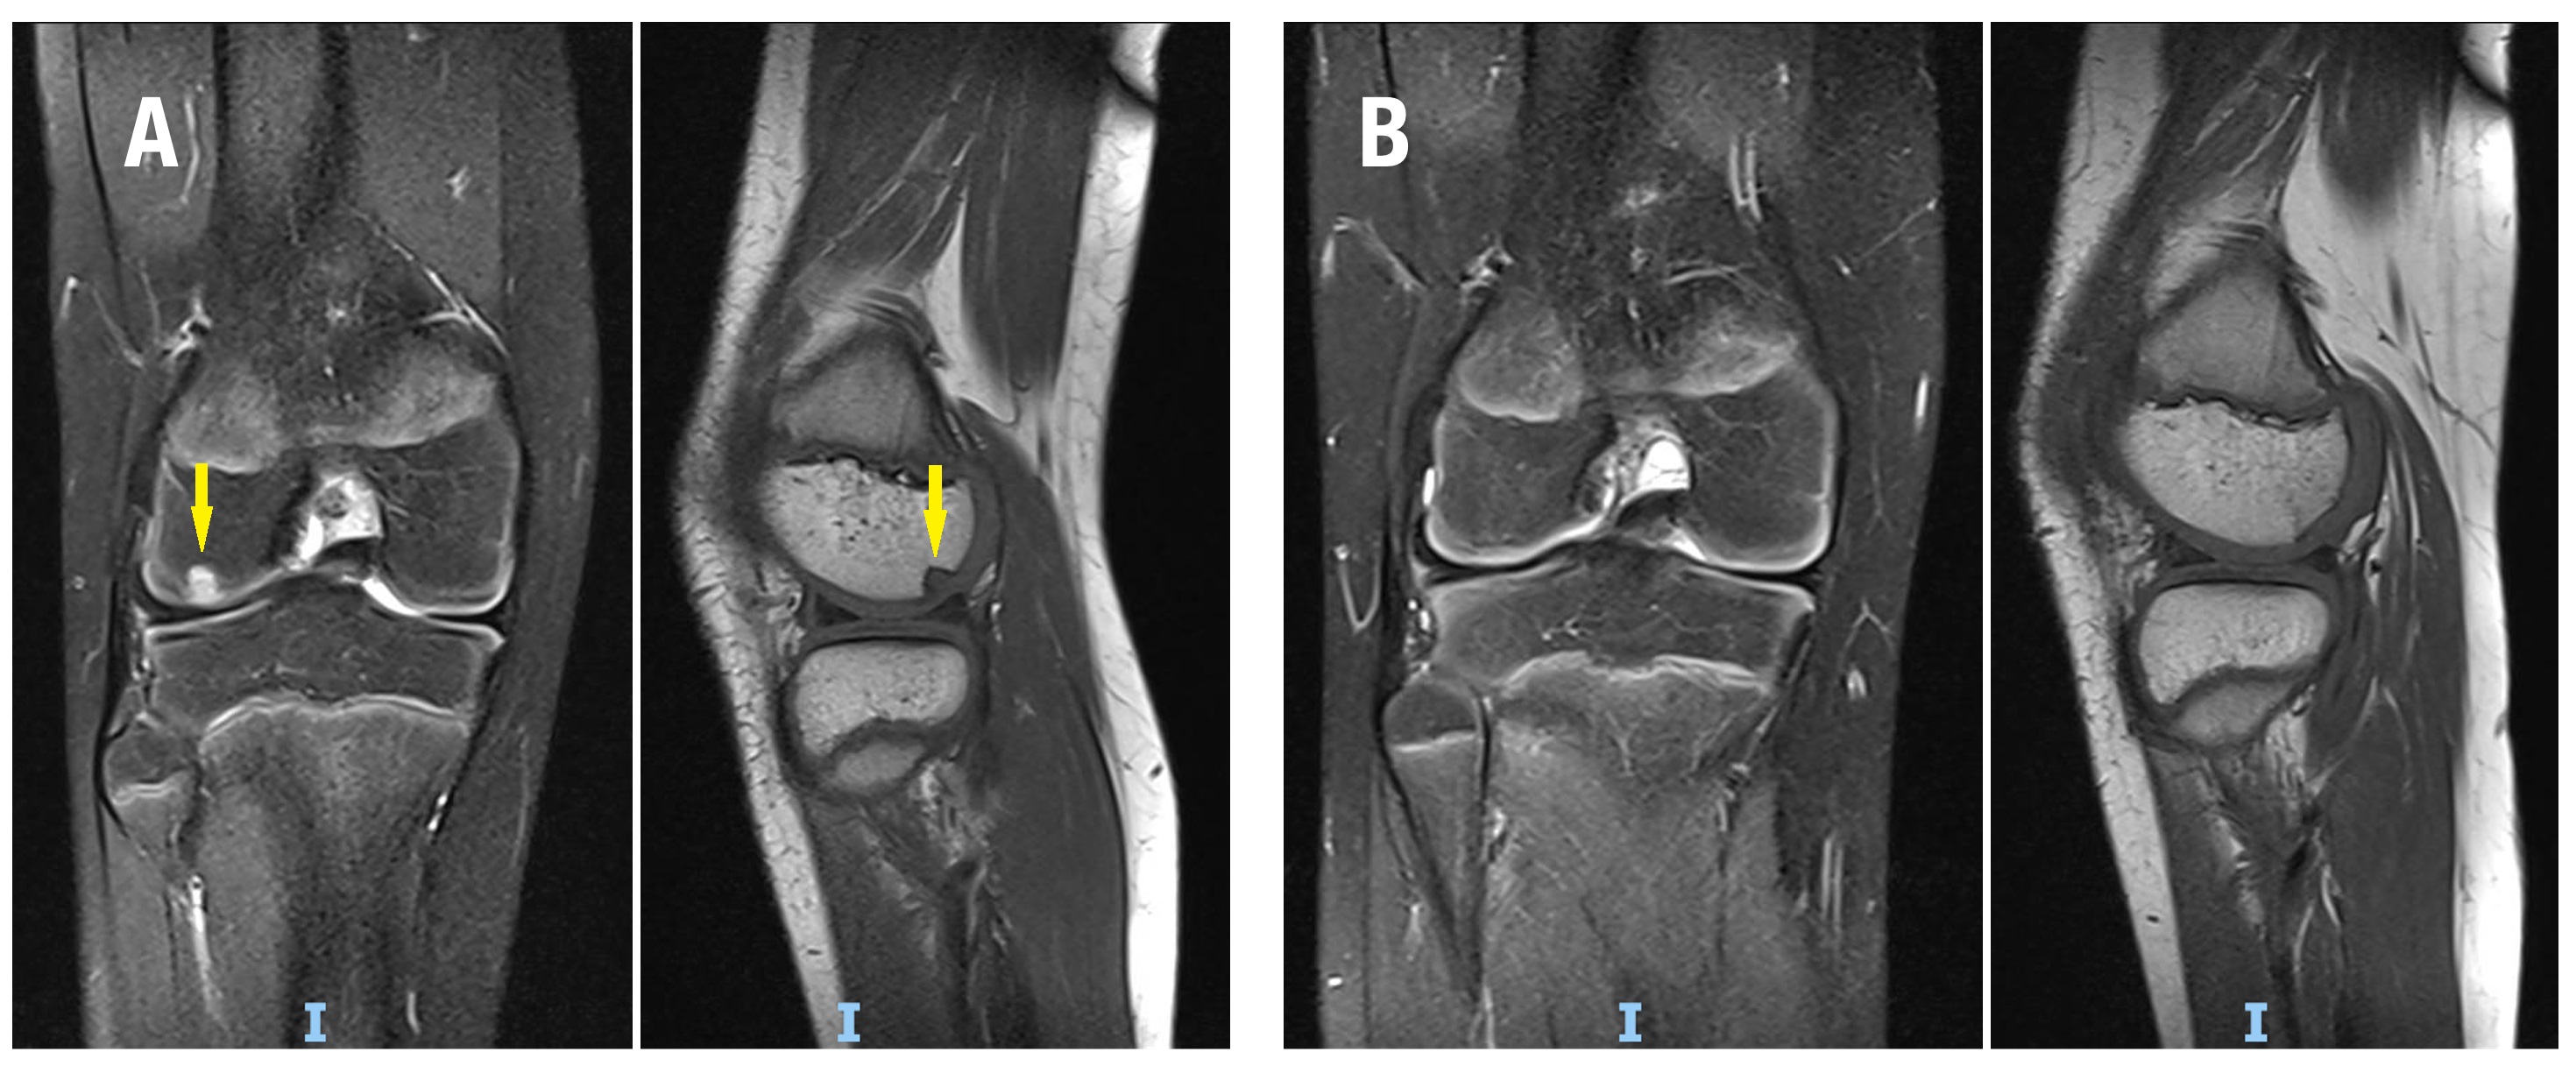

Figura 1. Trasplante osteocondral autólogo en una paciente de 10 años con defecto osteocondral de cóndilo femoral externo. A) Imagen preoperatoria de RNM DPFS (coronal) y T1 (sagital) donde se observa el defecto (flecha amarilla). B) RNM DPFS (coronal) y T1 (sagital) a los 6 meses, se observa incorporación completa del injerto.

En promedio, se trasplantaron entre 1 y 3 injertos osteocondrales cilíndricos por rodilla, con un diámetro promedio de 8 mm (rango, 6-10 mm). Diecisiete rodillas se trataron para DC (Fig. 1) y 16 mediante FH (Fig. 2) de lesiones osteocondrales inestables. Las lesiones tratadas con la técnica DC tuvieron un tamaño promedio de 132 mm2, significativamente menor que las lesiones de FH, con un tamaño promedio de 404.1 mm2 (p <0.0001). El seguimiento promedio de la cohorte fue de 20.5 meses (rango, 6-80 meses). No se registraron complicaciones perioperatorias.